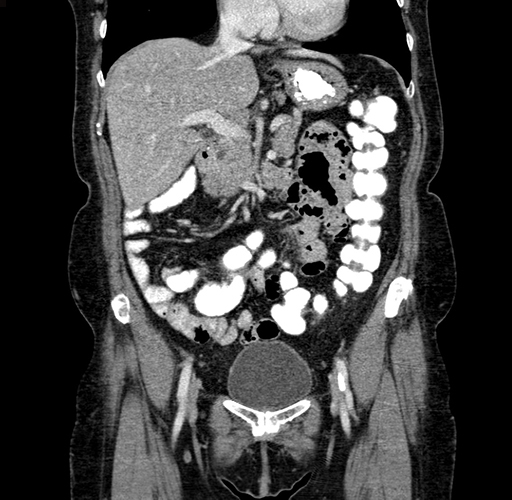

Pre-Chemo: Axial Venous

Axial Venous